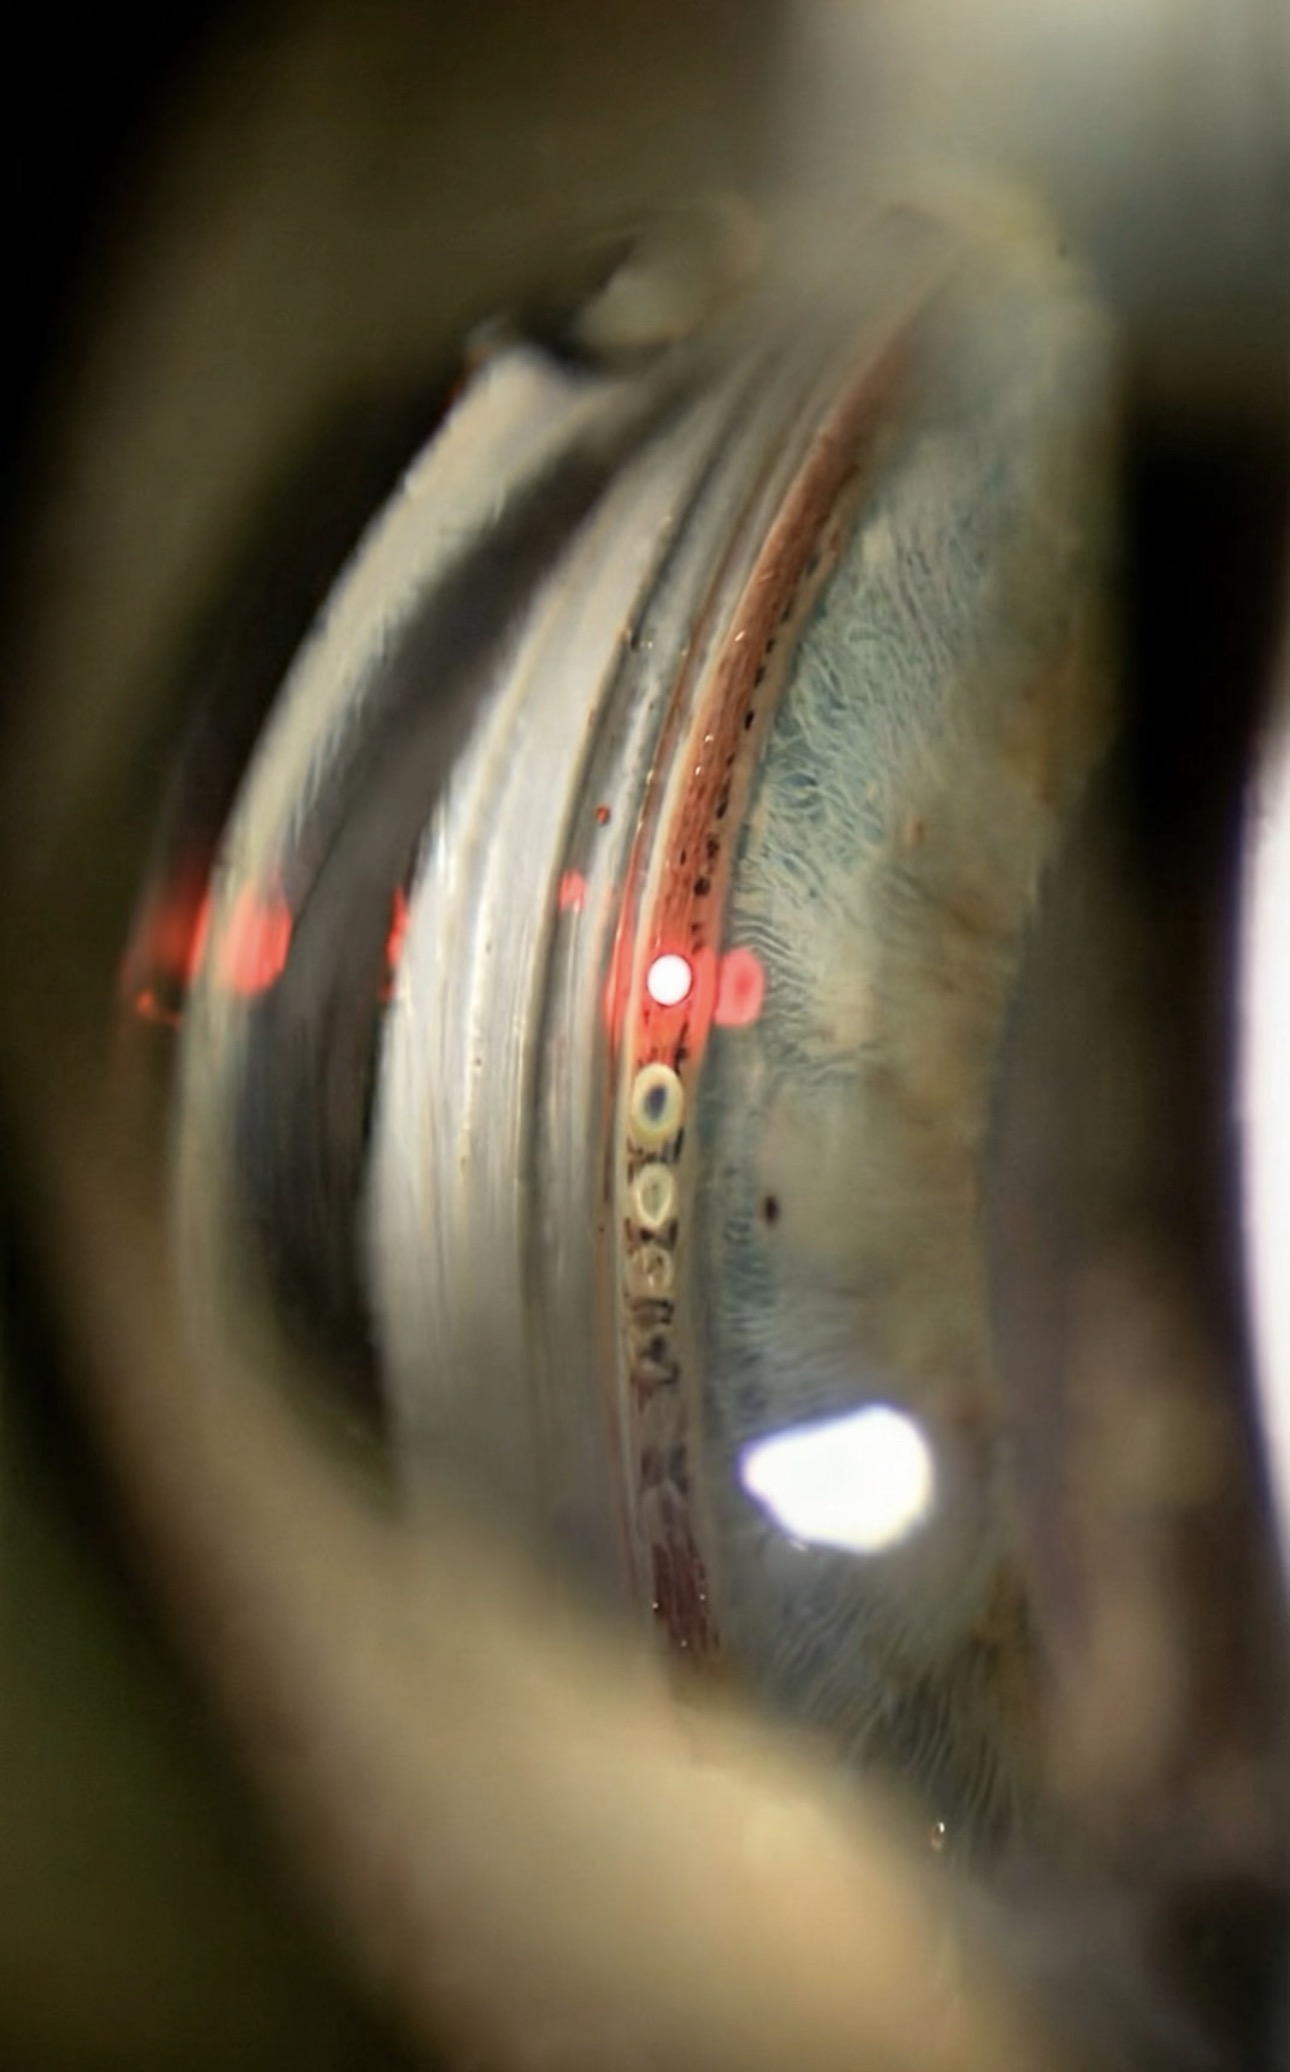

Genellikle ergenlik döneminde başlayan ve 40'lı yaşlara dek sessizce ilerleyebilen keratokonus, zamanında tanınmazsa kornea nakline kadar gidebilen bir hastalıktır. Sürekli değişen gözlük numarası ya da düzelmeyen görme bulanıklığı bir uyarı işareti olabilir. Erken evrede uygulanan çapraz bağlama ile hastalığın seyri büyük ölçüde kontrol altına alınabilir.

Kornea hastalıkları çoğunlukla sinsi ilerler; gözde yanma, ışığa duyarlılık ya da bulanık görme gibi şikayetler ihmal edildiğinde tablo ağırlaşabilir. Enfeksiyondan distrofilere, yüzey bozukluklarından nakil gerektiren durumlara dek geniş bir yelpazeyi kapsayan bu alan, erken değerlendirmeyle çok daha geniş tedavi seçenekleri sunar.

Uygun hastalarda uygulanan çapraz bağlama (cross-linking), keratokonus ilerlemesini yavaşlatmak veya durdurmak amacıyla kullanılan en önemli tedavi seçeneklerinden biridir. Erken tanı bu süreçte kritik öneme sahiptir.